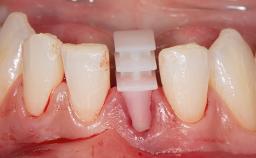

Immediate Replacement of Four Mandibular Anterior Teeth with a Conventionally Loaded Implant-Supported Fixed Dental Prosthesis

This case from German Gallucci, Adam Hamilton, and Teresa Chanting Sun details immediate placement with a conventional loading protocol (type 1C). It demonstrates a digital workflow combined with risk assessment to determine the best possible treatment approach for replacing mandibular anterior teeth.

A 63-year-old female patient was referred by a periodontist for consultation and assessment with regard to implant rehabilitation of the mandibular incisors. The patient presented in good health with no history of smoking or significant medical history. The patient’s chief complaint was mobility of the mandibular anterior dentition. She had a history of periodontal disease, which had been treated and followed by a periodontist with regular maintenance every four months over the previous ten years.